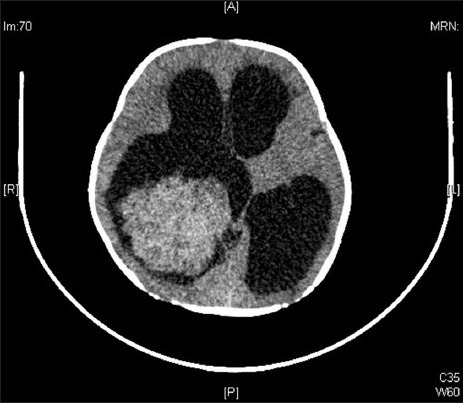

Puzzle 4

What's the Diagnosis?